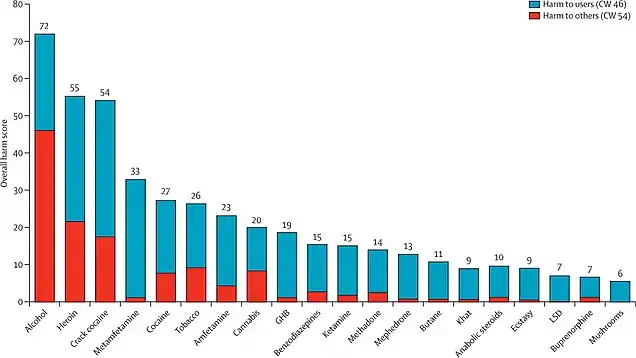

The NTFC stated that in their opinion, a total prohibition policy over-targets harm.[9] Current total prohibition policies (implemented in most Australian and US states) had been unsuccessful in reducing drug use and cause “significant social harm”. They are also associated with high financial costs of law enforcement.[2]

The NTFC recommended the Ministerial Council develop a national cannabis policy imposing civil penalties for personal use.[2][7] The NTFC justified a civil schemes application by arguing that the social and economic costs of enforcing criminal penalties on cannabis users far outweighed any benefits in deterring use or the harms arising from use. The Task Force cited that cannabis use was widespread, that its adverse health effects were modest and affected a minority of regular users, that criminal penalties did not affect the rate of cannabis use and that the majority of Australians supported the discontinued application of criminal penalties.[9]

In 1998, the Commonwealth Department of Health funded a report for the National Drug Strategy Committee which concluded that the social harm of criminal penalties far outweighed those arising under a civil scheme.[10] Criminal records in Western Australia were more likely to lead to further contact with the police (most likely because police had electronic access to these records), which adversely affected employment opportunities, accommodation choices and personal relationships. Criminal records also appeared to have no unique advantage in deterring use, with 87% of 68 convicted offenders continuing their use at the same rate as before six months later.[10]